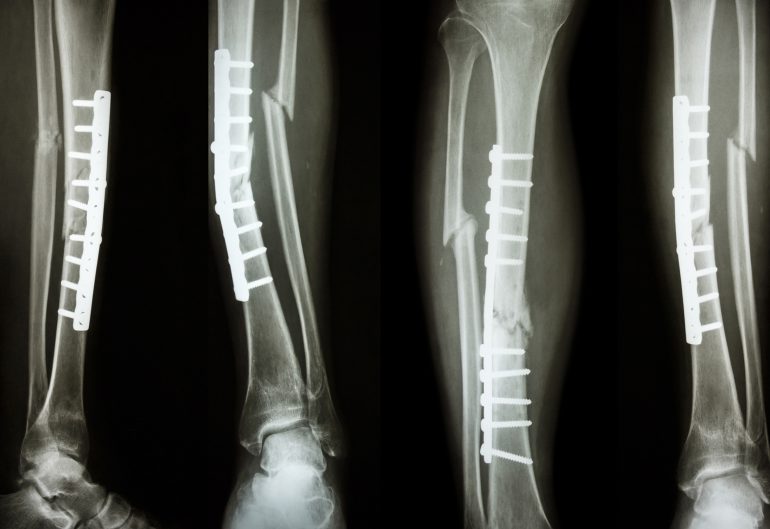

Move over metal plates and screws – ceramic could become the go-to graft for mending broken bones.

For the millions of people around the world who suffer from broken bones or bone loss from disease, deficiency or abnormal development, metal grafts can help things get back to some semblance of normal. But they come with downsides: they can cause discomfort, and they are sometimes rejected by the patient’s immune system.

The result is a 3D-printed ceramic implant with the same strength as bone, and over time the material dissolves and is replaced by real bone. This leads to less discomfort for patients and eliminates the need for additional surgery.